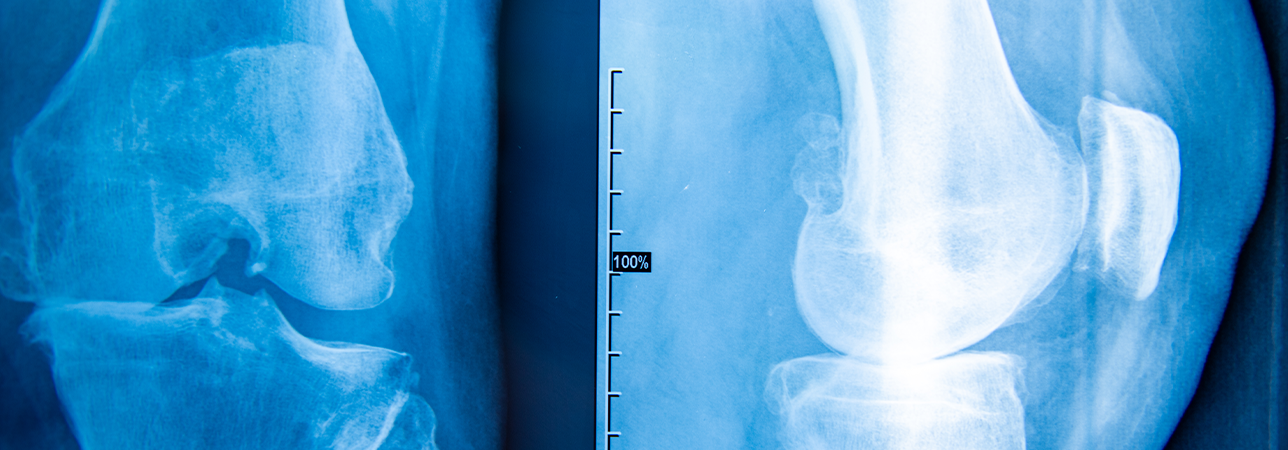

Diagnose: Zur Diagnose wird das Kniegelenk geröntgt und(oder eine Kniegelenk-MRT durchgeführt. Um weitere Verletzungen auszuschliessen oder die Stellung der Beinachse zu ermitteln, werden allenfalls zusätzliche Abklärungen vorgenommen.

Zur Diagnose eines Knorpelschadens wird das Kniegelenk geröntgt und eine Kniegelenk-MRT durchgeführt. Um weitere Verletzungen auszuschliessen oder die Stellung der Beinachse zu ermitteln, werden allenfalls noch weitere Abklärungen durchgeführt.